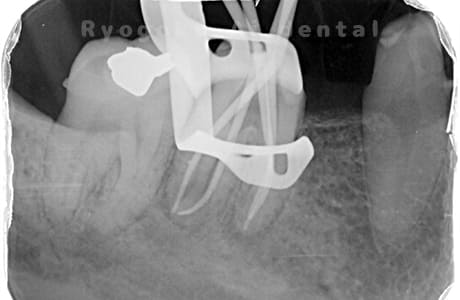

根管内の異物

- 原因

- 根管内異物(ファイル破折)による慢性根尖性歯周炎

- 治療期間

- 3ヶ月

- 治療内容

- マイクロスコープを使用した根管内異物除去並びにマイクロエンド

- 治療費用

- 121,000円(ファイル除去費用も込み)

他院で細い器具(ファイル)が根管内に破折した状態で、咬合痛を主訴に来院された患者様です。ファイルをマイクロスコープ下で除去し、根管治療を行ないました。